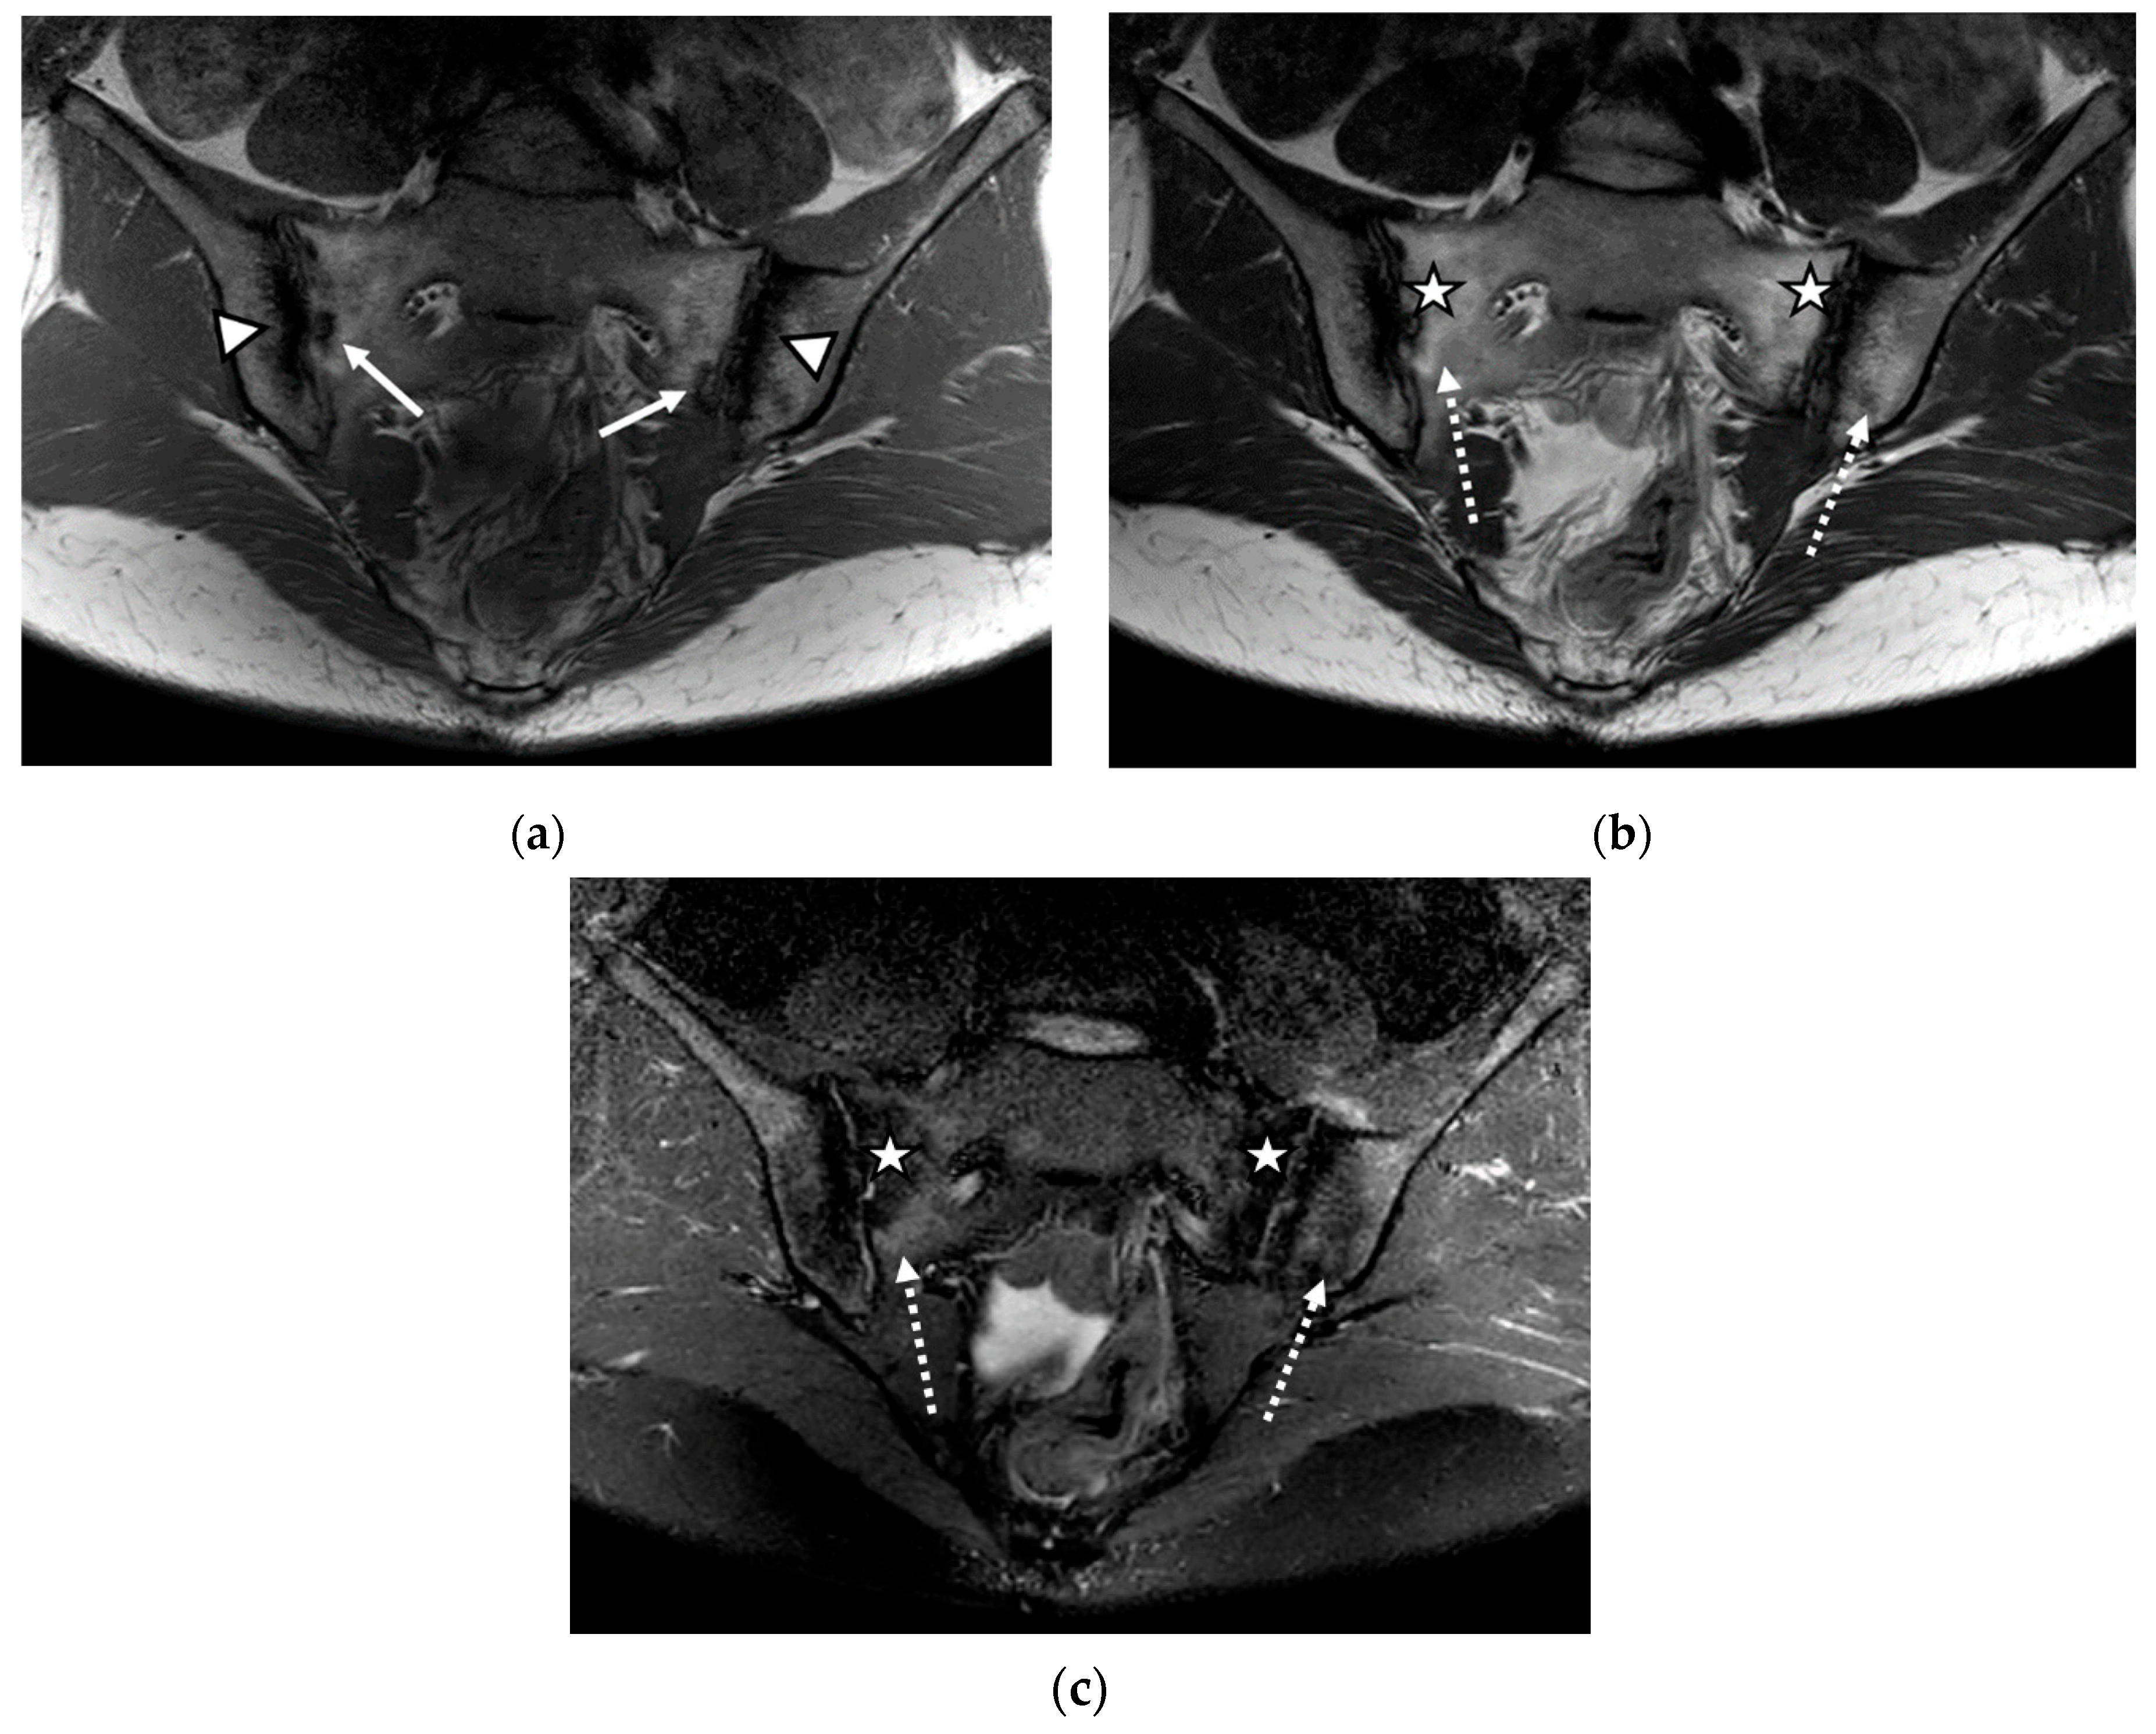

Figure 2.

The MRI scan of the sacroiliac joints indicated bilateral narrowing of the sacroiliac joint space, associated with bilateral subchondral sclerosis of the iliac bones (continuous arrow); bilateral fat metaplasia (asterisk), mostly affecting the iliac bones and the right part of the sacrum; backfill of the right sacroiliac joint space (arrowhead); diffuse bone marrow edema (discontinuous arrow), affecting the sacrum and the left iliac bone: (a) T1-weighted sequence; (b) T2-weighted sequence (without fat suppression); (c) STIR sequence.